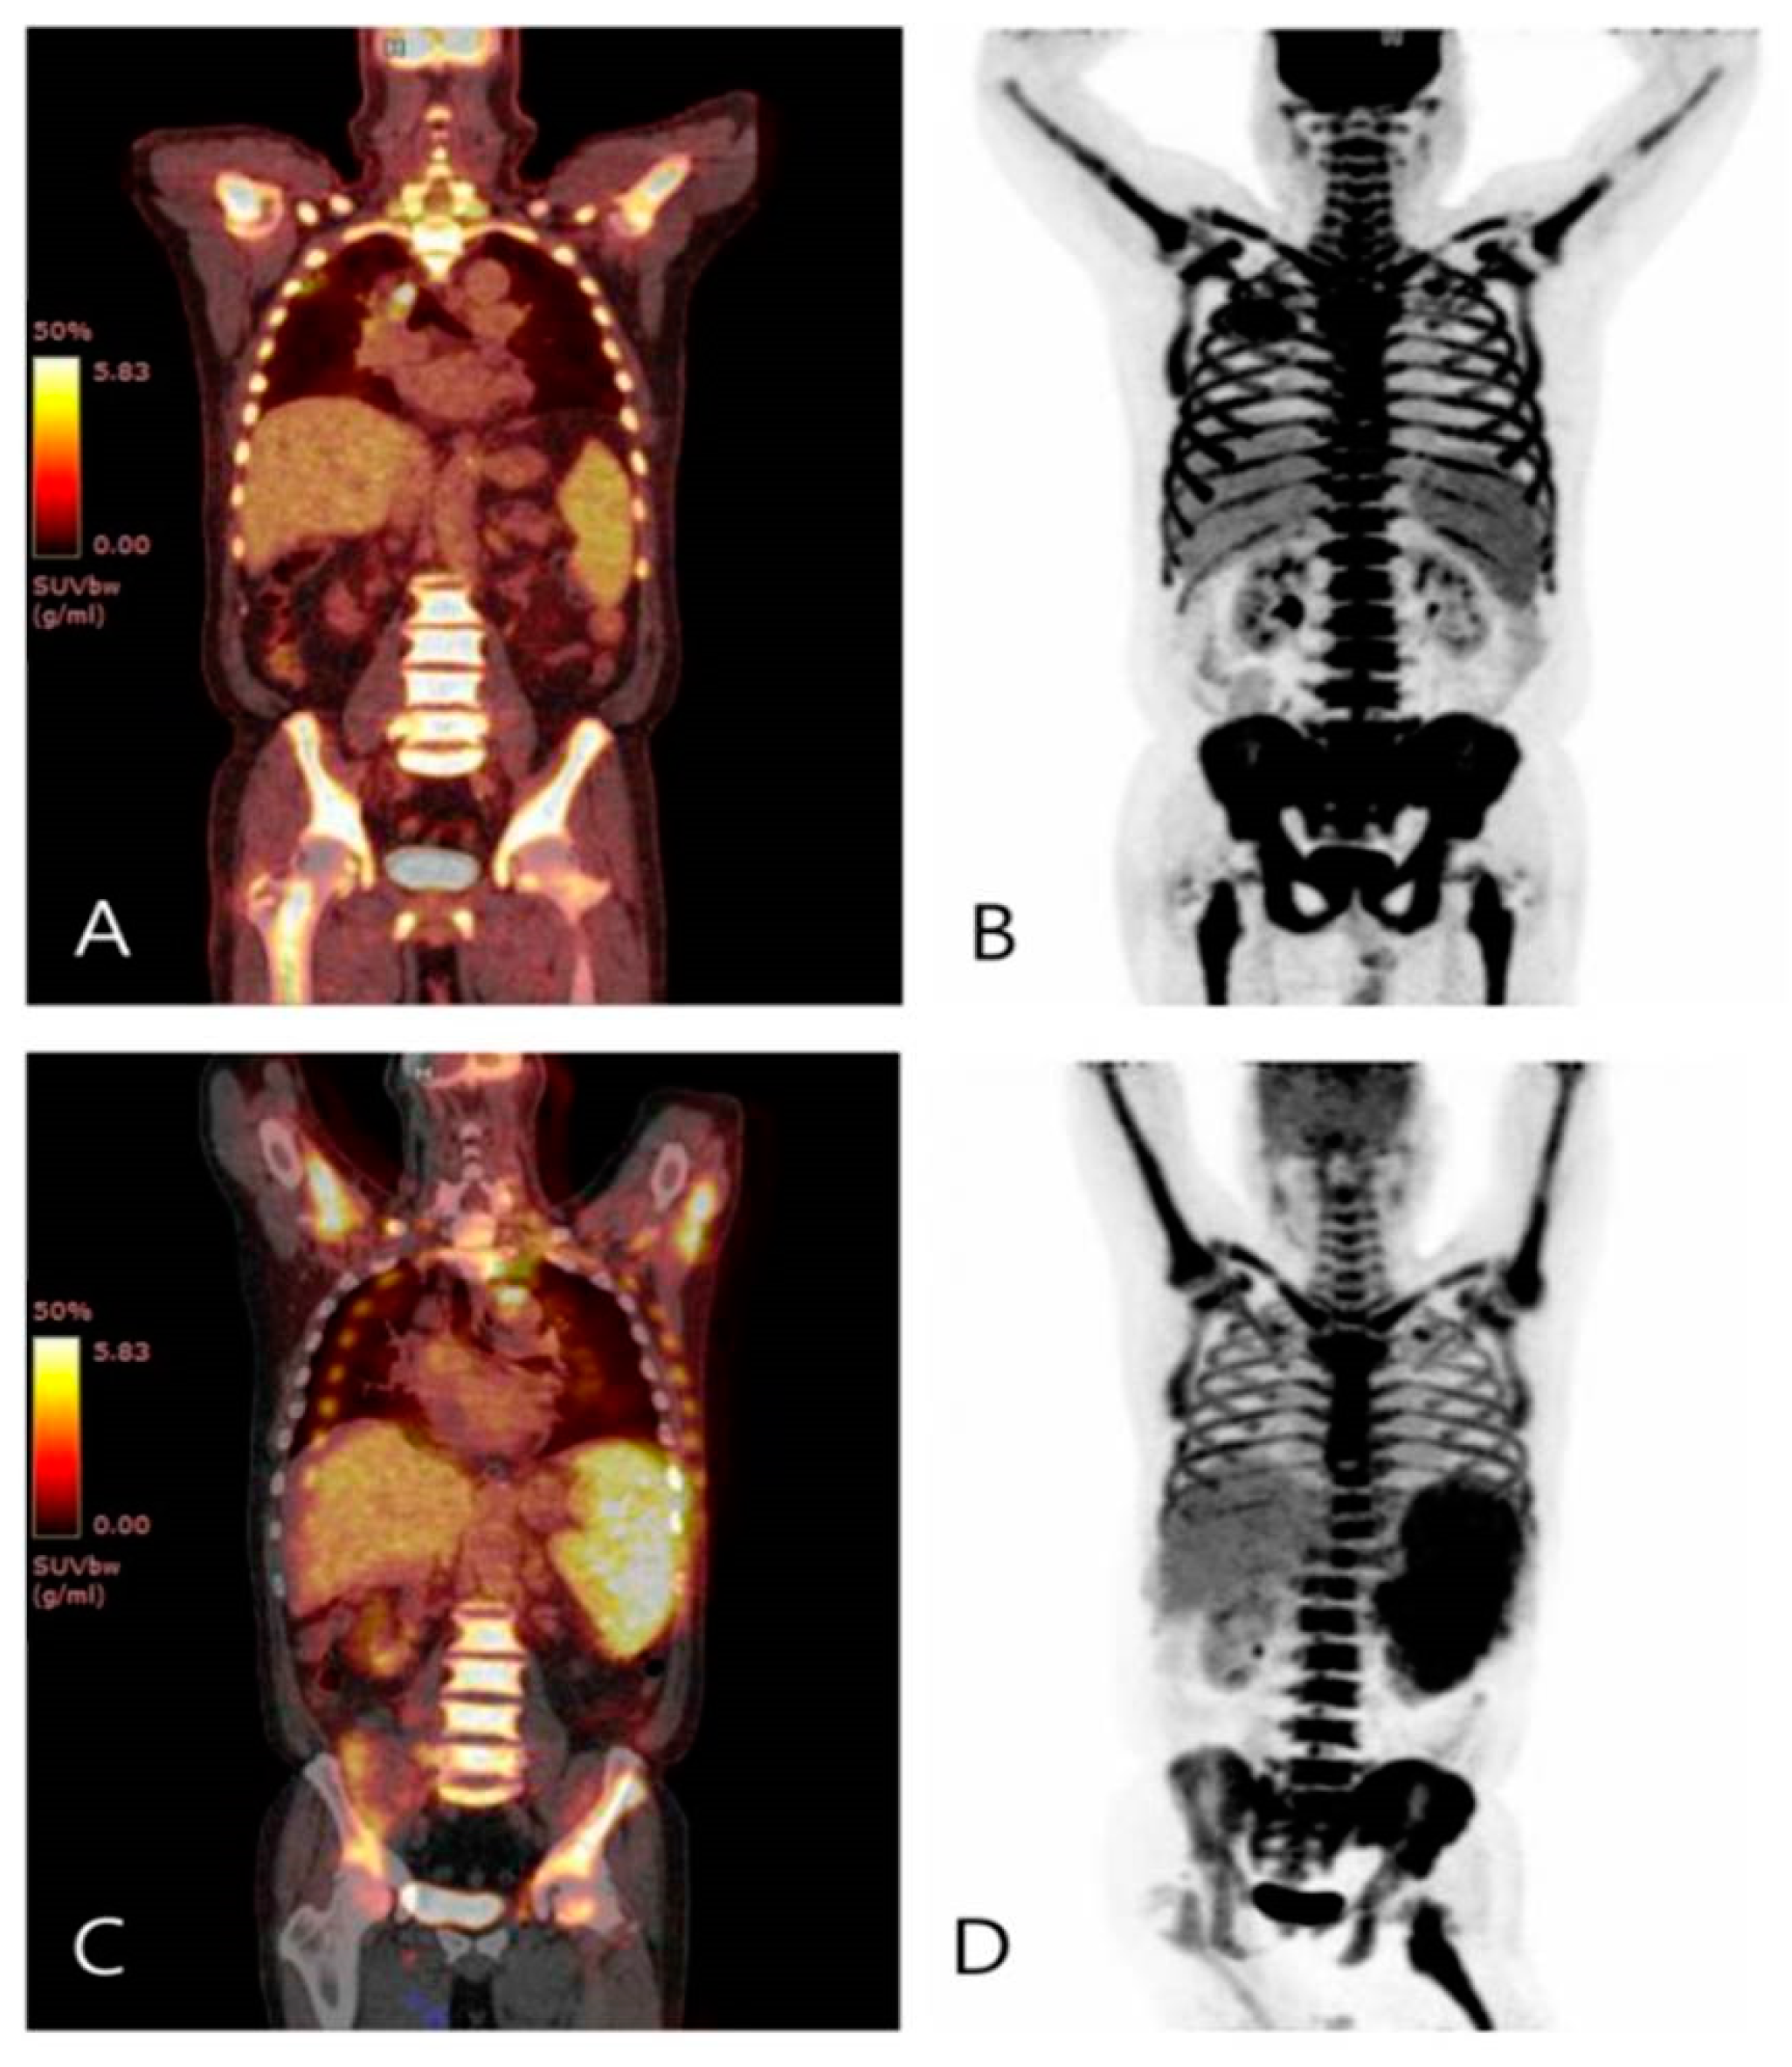

The value of 18 F‑FDG PET/CT in the prediction of clinical of Pet Ct Scan For Leukemia This test can show if any. As a useful imaging approach, pet significantly contributes to the diagnosis and treatment of different types of leukemia, especially in the. During a pet scan, a tracer (liquid that contains a small amount of radiation) is injected. A ct scan of the chest or abdomen can help detect an enlarged lymph node or cancers. Pet Ct Scan For Leukemia.

The value of 18 F‑FDG PET/CT in the prediction of clinical of Pet Ct Scan For Leukemia Some machines combine a ct scan with a pet scan (pet/ct scan). Cancer cells consume more of the tracer than do healthy cells, making them show up. A ct scan of the chest or abdomen can help detect an enlarged lymph node or cancers in the liver, pancreas, lungs, bones and spleen. As a useful imaging approach, pet significantly contributes. Pet Ct Scan For Leukemia.

The value of 18 F‑FDG PET/CT in the prediction of clinical of Pet Ct Scan For Leukemia A ct scan of the chest or abdomen can help detect an enlarged lymph node or cancers in the liver, pancreas, lungs, bones and spleen. As a useful imaging approach, pet significantly contributes to the diagnosis and treatment of different types of leukemia, especially in the. For a pet scan, glucose (a form of sugar) containing a radioactive atom is.. Pet Ct Scan For Leukemia.

The value of 18 F‑FDG PET/CT in the prediction of clinical of Pet Ct Scan For Leukemia During a pet scan, a tracer (liquid that contains a small amount of radiation) is injected. As a useful imaging approach, pet significantly contributes to the diagnosis and treatment of different types of leukemia,. Some machines combine a ct scan with a pet scan (pet/ct scan). This test can show if any. As a useful imaging approach, pet significantly contributes. Pet Ct Scan For Leukemia.